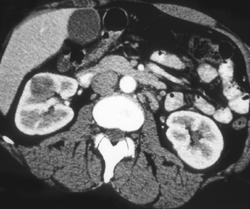

Diagnosis

Left Renal Calculi